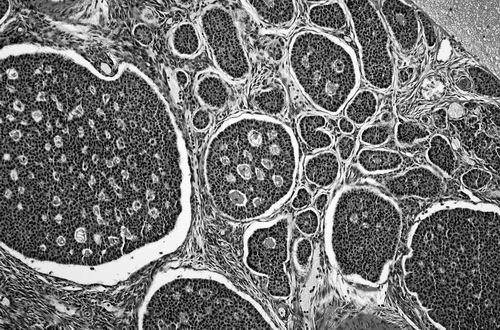

一项临床试验将对卵巢癌细胞进行改造,并将这些细胞重新输给患者。图片来源:PJD/SCIENCE SOURCE